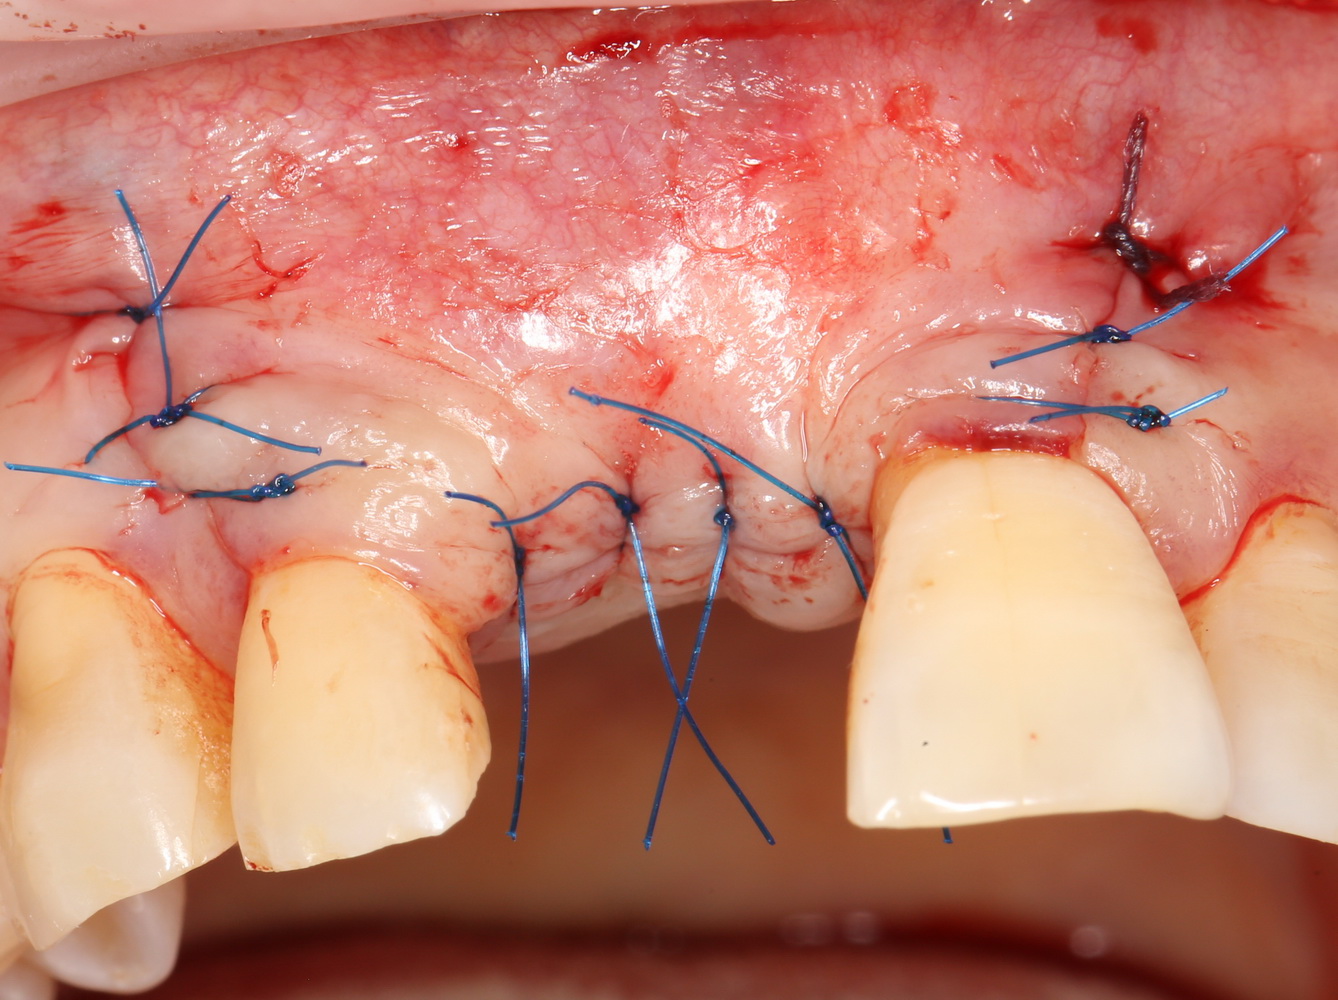

Ну и, швы:

Друзья, он очень простой. Это швы. От качества швов зависит очень и очень многое.

Если при работе с костными блоками в случае расхождения швов у нас есть шанс сохранить результат, то при попадании инфекции из полости рта в область трансплантата, состоящего из аутокостной стружки, он сам быстро превращается в рассадник инфекции — ни промыванием, ни повторными швами удержать объем и результат не удается. С этой точки зрения, описываемая методика гораздо более деликатная и ранимая. Инфекцией, разумеется.

Поэтому забываем викрил и другие плетеные материалы. Только нерезорбируемая мононить (Prolene, Resoprene и т. д.), только хардкор.